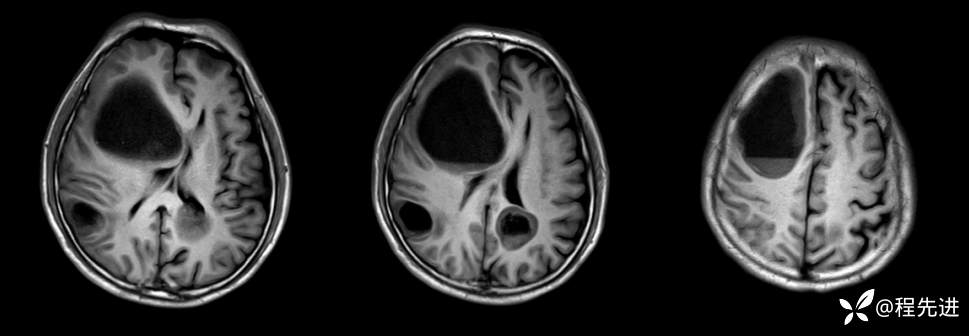

T1: